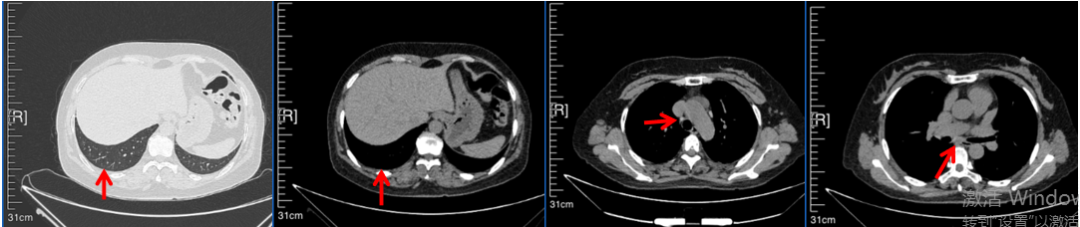

56岁,女性,无吸烟史饮酒史,既往体健。2023年02月患者体检发现肺占位性病变,胸部增强CT:右肺下叶后基底段结节;右侧锁骨上及纵隔内多发淋巴结肿大。PET-CT:右肺下叶周围型肺癌可能性大;1R、2L、3P、4R、4L及7组淋巴结转移可能性大。2023年02月就诊于本院胸外科行超声胃镜下纵隔肿物穿刺活检术,病理:结合免疫组化,符合肺腺癌。行NGS基因检测:EML4:exon20-ALK:exon20融合。PD-L1(克隆号22C3)TPS=55%。

临床诊断:右肺下叶恶性肿瘤cT1bN3M0,IIIB(第9版分期),纵隔淋巴结继发恶性肿瘤,锁骨上淋巴肿继发恶性肿瘤

治疗经过:2023年3月27日始行恩沙替尼靶向治疗至今,最佳疗效为PR,末次评效为维持PR。期间出现轻度肝功能异常(DILI 1级),对症处理后好转。截止目前PFS为26个月。

2023年2月20日基线检查

2024年6月复查PR(最佳疗效)